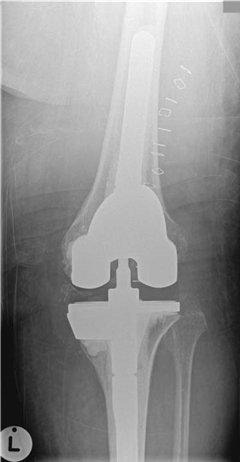

Illustration 9 for Ace FRCS Orthopaedics: Oxford University Press Adult Pathology Viva

๐Ÿ” Click to enlarge

Clinical Radiograph / Orthopedic Image

What are the commonest causes of pain following a TKR?

This is still fairly early after a TKR and many patients still have pain that continues to resolve at this stage. Causes include:

z Infection โ€” may not be commonest but is the most important to exclude z Patellofemoral problems z Component mal-position (overhang, mal-alignment, poor cementing) z Loosening z Complex regional pain syndrome (CRPS) z Instability

z Dual pathology (hip arthritis)

How would you investigate and manage this patient?

C areful history: this needs to include an assessment of the patient prior to the TKR. The intra-operative and immediate post-operative care, including wound healing, length of stay, and any reported complications. Has there been a period when the knee was any good? How is the knee now (startup pain)? Are there any co-morbidities โ€” infection is more likely with diabetes mellitus (DM), RA, steroids

Examination: effusion/haemarthrosis, alignment, soft tissues, CRPS, ROM, PF tracking, patella clunk, balance, flex/extension mismatch, tender areas, hips.

Investigations:

z X-ray: component sizing, tibial overhang, femoral sizing, patello-femoral joint overstuffing, patella subluxation, loosening/infection, fractures, heterotopic ossification

z Blood tests: CRP, ESR z Bone scan: no help at 6 months z CT scan: may help assess rotation of components z Aspiration/biopsy: if there is infection z Arthroscopy: if a treatable cause is identified

The blood tests show raised CRP and ESR, and the aspirate grows coagulase-negative, Gram-positive cocci after 5 days. How do you manage this?

T his seems to be a prosthetic infection with Staphylococcus epidermidis. I would discuss with the patient the diagnosis, the various treatment options, and the possible outcomes (function, further surgery, best- and worst-case scenarios). The treatment options would depend on the patientโ€™s physiological status and wishes:

Debride and retain

Revision (single stage or two stages)